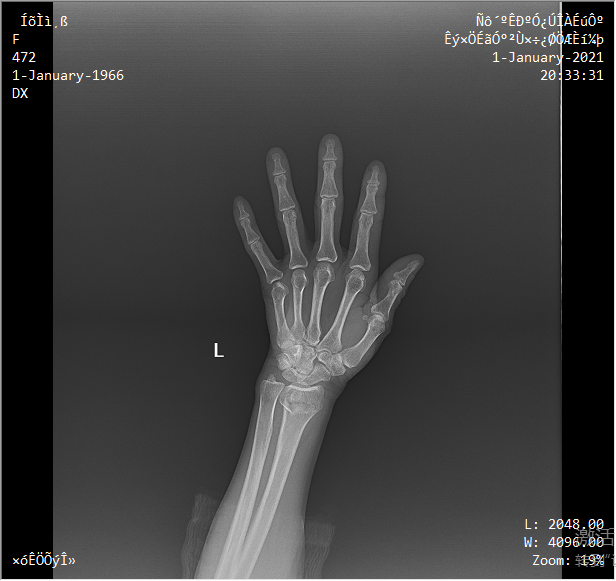

采用靈活的懸吊式機(jī)架設(shè)計,配置電動升降攝影床/移動床與高品質(zhì)平板探測器,實現(xiàn)圖像與擺位的有機(jī)統(tǒng)一,可應(yīng)用于DR攝影多種臨床X線檢查領(lǐng)域。

醫(yī)生選擇需要拍攝的部位,自動生成擺位示意圖像,引導(dǎo)病人快速準(zhǔn)確的完成擺位。

依據(jù)臨床圖像庫自動進(jìn)行圖像后處理,呈現(xiàn)效果佳。